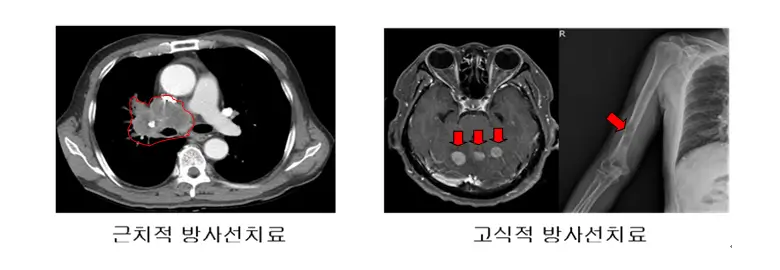

방사선치료는 고에너지의 방사선을 이용해 암세포를 죽이는 방법입니다. 주로 비소세포폐암의 초기 단계나 소세포폐암의 제한적 병기에 사용됩니다. 방사선치료는 국소 부위에 높은 에너지를 집중시켜 암세포의 성장을 억제하거나 파괴하는 데 효과적입니다.

방사선치료의 종류

방사선치료에는 외부 방사선치료와 내부 방사선치료가 있습니다. 외부 방사선치료는 몸 바깥에서 방사선을 쏘아 암을 치료하며, 내부 방사선치료는 방사성 물질을 암 조직 근처에 삽입하여 치료합니다.